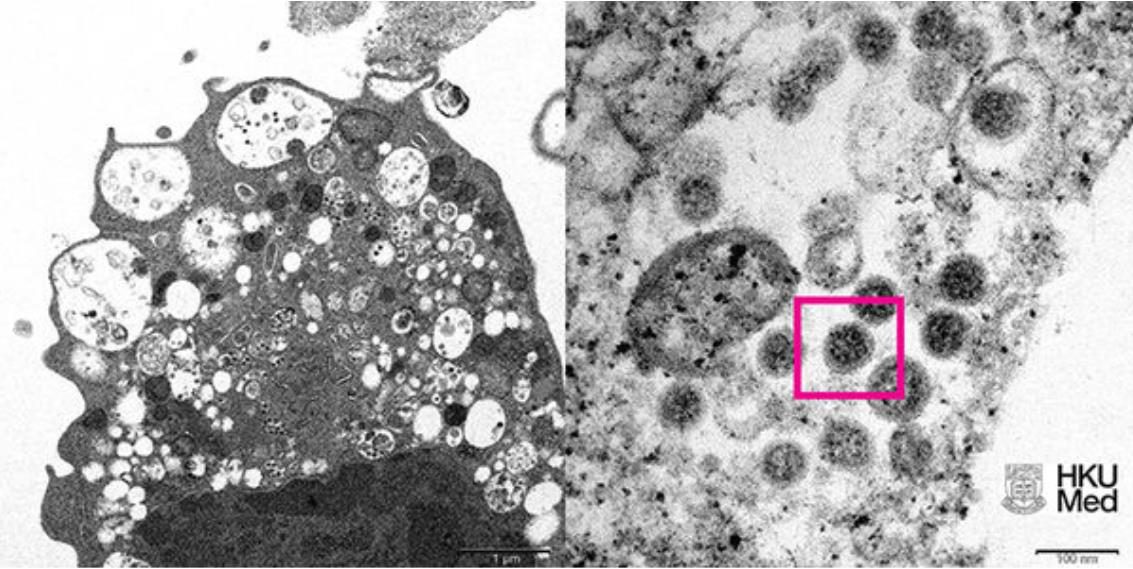

香港大学公布的Omicron变种病毒显微镜下成像

▲香港大学公布的Omicron变种病毒显微镜下成像。(图/澎湃新闻)

香港大学今(8)日发布新冠变种病毒Omicron在显微镜下的真实面貌,分别为低倍电子显微镜所呈现的感染新型冠状病毒Omicron变种毒株后的猴肾细胞(Vero E6)及高倍电子显微镜下受感染的Vero E6细胞。此外,港大在1日也率先成功从临床标本中分离出Omicron病毒,成为亚洲首个揭开该病毒神秘面纱的团队。

《澎湃新闻》报导,根据港大公布的照片显示,图左照片为低倍电子显微镜下感染新型冠状病毒奥密克戎(Omicron)变异株后的猴肾细胞(Vero E6)。照片显示细胞受损,肿胀囊泡,囊泡内含有黑色小病毒颗粒。显示细胞受损,肿胀囊泡,囊泡内含有黑色小病毒颗粒。

图右照片则为高倍电子显微镜下受感染的Vero E6细胞。照片显示病毒颗粒表面呈现皇冠形的刺突蛋白(红框处)。

此前,香港大学微生物学系团队成功从临床标本中分离出Omicron病毒,为亚洲首个揭开该毒株神秘面纱的团队,有助于开发和生产灭活全病毒疫苗,阻截变种病毒疫情蔓延。